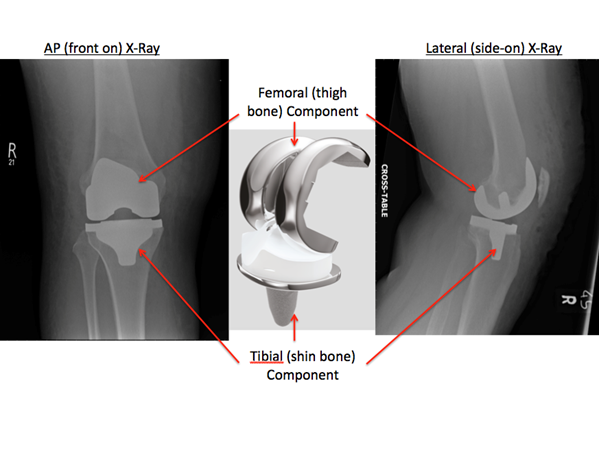

The joint surfaces of the 3 compartments of the knee are replaced in this procedure. On occasions the patella (kneecap) which forms part of the patello-femoral compartment does not need to be replaced.

The articular surfaces of the knee joint are shaved and each surface is replaced with an implant made of metal or plastic.